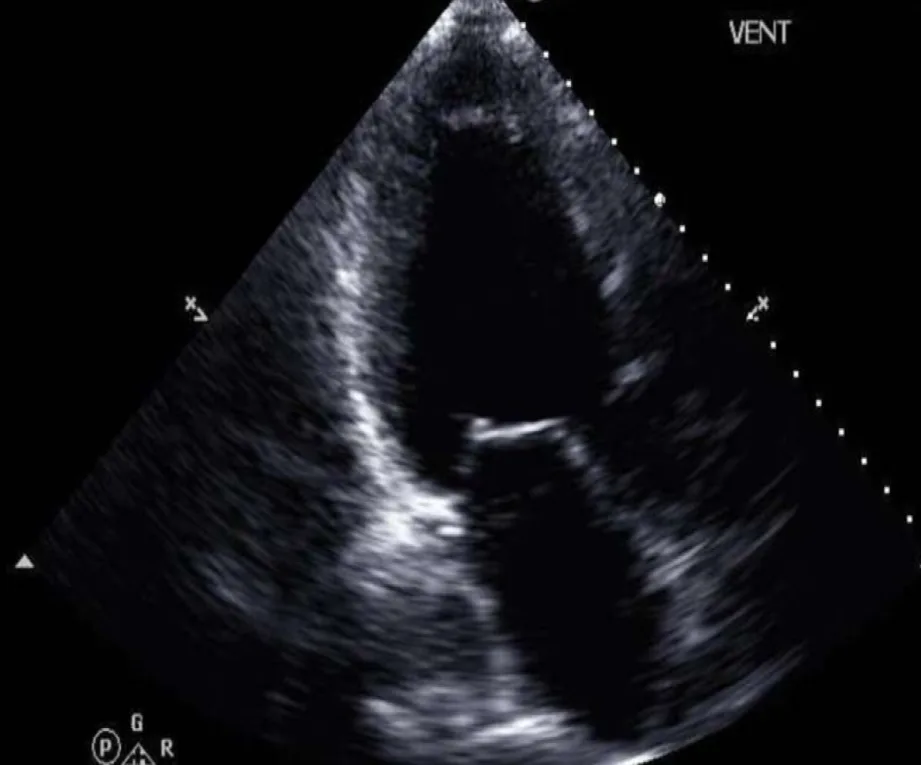

En el nuevo estudio, publicado el 3 de marzo en npj Digital Medicine, los investigadores probaron un novedoso método basado en inteligencia artificial que podría eliminar este obstáculo. El nuevo método predice con alta precisión la medida más importante de la prueba de esfuerzo cardiopulmonar (CPET), el consumo máximo de oxígeno (VO₂ pico), utilizando imágenes de ultrasonido del corazón del paciente, mucho más fáciles de obtener, además de su historial clínico electrónico.

Utilizar la IA en datos de ultrasonido cardíaco para ayudar a identificar pacientes con insuficiencia cardíaca avanzada parecía una de las aplicaciones más prometedoras. El Dr. Uriel contactó entonces con expertos en IA de Cornell Tech, Cornell Bowers y Weill Cornell Medicine, quienes desarrollaron el nuevo modelo de aprendizaje automático tras varios años de colaboración.

El equipo de IA liderado por el Dr. Wang, que incluye a los autores principales, el Dr. Zhe Huang y el Dr. Weishen Pan, junto con estudiantes y profesores de Cornell Bowers, desarrolló un modelo de aprendizaje automático multimodal y multiinstancia que puede procesar varios tipos de datos distintos, incluidas imágenes ecográficas en movimiento ordinarias del corazón, imágenes de formas de onda relacionadas que muestran la dinámica de las válvulas cardíacas y el flujo sanguíneo, y varios elementos que se encuentran en los registros médicos electrónicos.